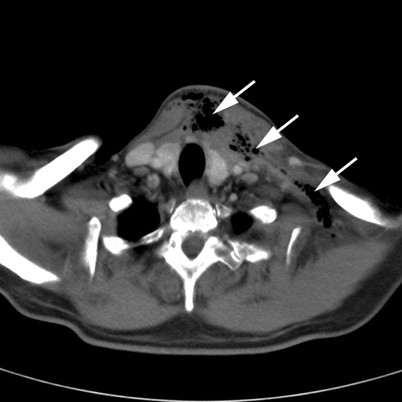

Ein Peritonsillarabszess kann aber auch Ausgangspunkt schwerer Komplikationen sein wie Abszesse der Halslymphknoten, Ausbreitung der Entzündung entlang der Gefäßscheide des Halses mit Entwicklung einer Thrombophlebitis und der Gefahr einer Sepsis sowie das Lemierre-Syndrom. Besonders gefürchtet ist eine Ausbreitung der Entzündung in den Spatium peripharyngeum, weil dieser ohne Grenze mit dem Mediastinum in Verbindung steht und sich die Entzündung auf diesem Wege leicht in den Brustraum ausbreiten kann.